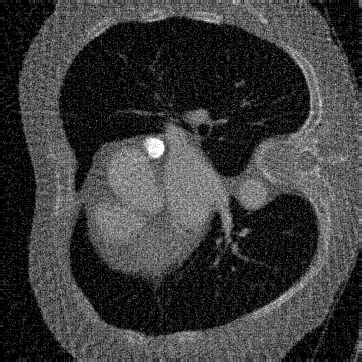

4.2 Forward and Noise Models

We consider two (inverse) problems: denoising and CTreconstruction. The latter has become one of the most accessible imaging modalities in non-destructive testing, security, and medicine. For denoising, it holds that 𝐇=𝐈\mathbf{H}=\mathbf{I}. Additionally, the images 𝐱[0,1]d\mathbf{x}\in[0,1]^{d} are corrupted by additive Gaussian noise 𝐧\mathbf{n} with standard deviation σ=0.1\sigma=0.1. Regarding our CTreconstruction experiment, recall that a scanner acquires multiple measurements while rotating around an object. We model a sparse-view setting, where 𝐇\mathbf{H} is given by the discretized X-ray transform with 60 equispaced angles and a parallel beam geometry. We use the DeepInverse implementation. To keep the setup simple, we consider Gaussian noise with σ=0.7\sigma=0.7 instead of more realistic Poisson noise. For our ground truth images 𝐱[0,1]d\mathbf{x}\in[0,1]^{d}, the measurement range is between 0 and 400. In both settings, we use the data-fidelity D(𝐇𝐱,𝐲)=12𝐇𝐱𝐲2D(\mathbf{H}\mathbf{x},\mathbf{y})=\frac{1}{2}\|\mathbf{H}\mathbf{x}-\mathbf{y}\|^{2}. For CTreconstruction, taking the pseudo-inverse 𝐇\mathbf{H}^{\dagger} is also known as filtered backprojection (FBP).

For the CTreconstruction experiments, we consider the LoDoPaB-CT dataset [89]. Its ground truth images of size 362×362362\times 362 are based on reconstructions in the LIDC/IDRI database [13]. While the original dataset is very large, we use the 35223522 images from the validation set for training, and the 128128 images from the first test batch for testing.